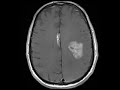

Pericallosal Lipoma

These images show a midline pericallosal T1 hyperintense, T2 FLAIR hyperintense mass which is hypointense on T2 fat saturated images compatible with a lipoma. This finding is incidental as the patient is being followed for the larger, more ominous heterogeneously enhancing mass with perilesional edema in the left cerebral hemisphere compatible with a glioblastoma. The pericallosal location for this lipoma is the most common site for intracranial lipomas and can be seen with anomalies of the corpus callosum.